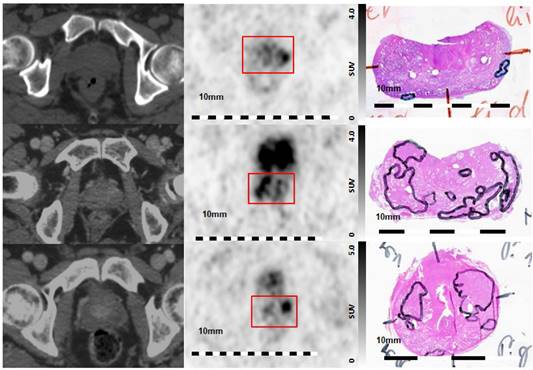

Visual evaluation showed moderate to good overlap between PET and histopathology in eight of nine patients, with the exception of patient five (Figure 4). Voxel-wise analysis of spatial agreement between PSMA PET and histo-PET revealed mean R² of 55 % ± 16 % (median 57 %, range: 7 - 82 %, p < 10-5 for all, Figure 5).

Figure 4

Visual Evaluation of spatial correlation between PSMA PET and histopathology. Step sections were coregistered to 68Ga-HBED-CC-PSMA PET images Left column: axial CT images, middle column: corresponding axial 68Ga-HBED-CC-PSMA PET images, right column: corresponding histopathological slices (manual coregistration). Upper line: poor overlap between PET and histopathology in patient 5. Note the small and lentiform shaped tumors. Middle line: good overlap of PET and histopathology in patients 1, and lower line: moderate overlap in patient 9. Red box: area of prostatic gland in PET images.

Patient 5 had similar clinical characteristics as the other patients (Table 1) but were characterized by several small and lentiform PCa lesions in histopathology. Visual correlation between PSMA PET and histopathology (Figure 4, upper row) revealed a small left peripheral lesion on histology, while the left-sided PET focus appeared disporportionally large. The lesion on the right side was missed by PET. This disagreement can also be appreciated by inspection of the scatter plot in Figure 5, showing corresponding vertical and horizontal extensions, respectively. The lack of detection of the very small, lentiform right-sided lesion may be explained by PET resolution limitation [37], while the discrepantly larger PET focus on the left side could be due to incomplete histopathological coverage. Small-size lesions with less than 4-mm thickness (distance between two step-sections) may not be appropriately covered by histopathology, while still causing focal uptake on PET.